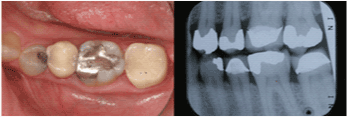

| Mandibular Right First

Molar |

10 |

67.0% |

|

| Maxillary Left First

13 |

70.9% |

| Mandibular Left First

8 |

73.8% |